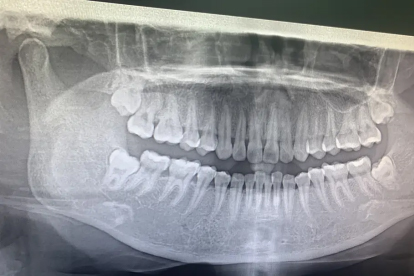

父母存在智齿阻生史时,子女智齿异常萌出概率较高。基因决定牙胚发育方向和颌骨大小,可能引发智齿横向或倒置生长。建议青春期后拍摄全景片评估智齿位置,提前干预。

智齿牙胚形成期受辐射、创伤或感染等因素干扰,可能造成牙根弯曲、牙冠畸形等发育缺陷。这类智齿易形成含牙囊肿或引发神经压迫,需通过CBCT检查明确解剖关系。